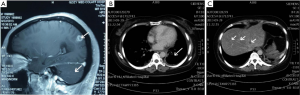

Molecular target treatment was initiated on August 29, 2013 and the patient was given oral Crizotinib, with a dose of 250 mg, twice a day. Also, whole brain radiotherapy (WBRT) alongside in-field boost (6) commenced on August 29, 2013. The repeated MRI reported that the metastases of cerebrum and cerebellum have markedly decreased in size (Figure 3A).

However, Crizotinib also led to some side effects, though minor ones. Although a chest CT scan showed that the tumors on the left lower lobe and hepatic had reduced significantly, along with the mediastinal lymph nodes and hilus pulmonis lymph node (Figure 3B,C), the patient experienced a low-grade fever, chest tightness, shortness of breath and Karnofsky performance status (KPS) (7) rating falling to 60 point. The lung exudative lesions had increased in size (Figure 4A). Considering the symptoms like wet rales and shortness of breath, the history of Crizotinib administration, imaging findings and lack of bacterial growth found on multiple sputum cultures, a diagnosis of Crizotinib-induced level 4 interstitial pneumonia (Common Terminology Criteria for Adverse Events, v.3.0) was performed. The patient was therefore administered with dexamethasone 10 mg plus cefuroxime 2.0 mg twice a day and oxygen inhalation. Quick medical follow-up and treatment could reduce the chest tightness and shortness of breath. Significantly, a rise on KPS score was witnessed, whereby improving the symptoms. CT scan showed that the pulmonary exudative lesion area disappeared in contrast with the results of the previous scan lesion area (Figure 4B,C). Finally, on October 14, 2013, the patient was discharged from the hospital accounting for the signs of recovery. And continuous treatment with lower dosages was still needed.